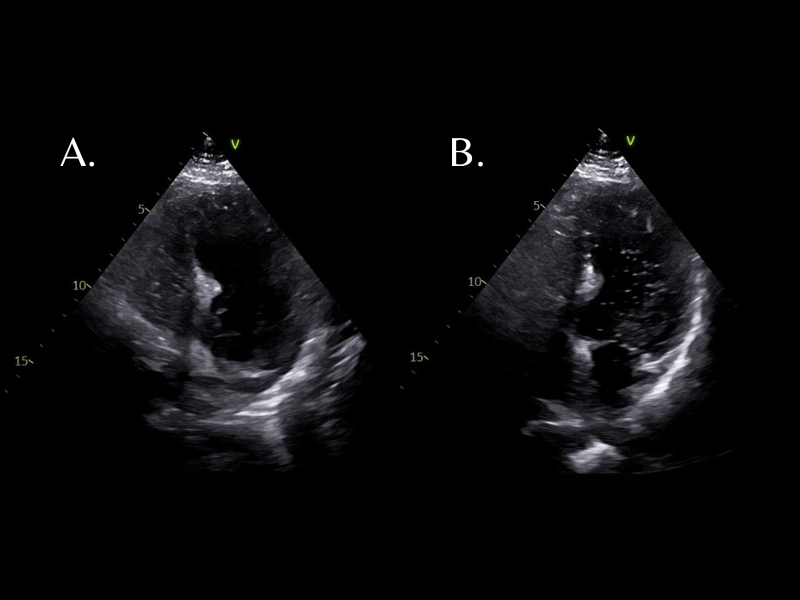

An echocardiogram with bubble study was performed, with bubbles seen in both the left and right ventricle within three cardiac cycles, suggestive of an intracardiac shunt. The patient did not have any history of liver disease or known structural heart disease. The patient underwent an intracardiac echocardiogram which confirmed the large right to left shunt via patent foramen ovale and was closed with a septal occluder. The patient’s oxygen needs resolved immediately post-procedure and he was discharged in good condition on hospital day 7.

The initial workup of the shunt causing POS is an echocardiographic bubble study with agitated saline.7 A normal bubble study will have bubble opacification of the right ventricle but not the left ventricle. The bubble test is considered abnormal and concerning for a shunt if bubbles appear in the left ventricle within 3 cardiac cycles, whereas non-cardiac shunts are suspected if there are more than 5 cardiac cycles before bubbles appear.5 If the test is normal but suspicion remains high, there is limited evidence to suggest that an agitated D50 bubble test may be more sensitive in detecting smaller shunts, as D50 bubbles are smaller and more uniform than those of normal saline.8 However, some cases may require contrast tilt-table transesophageal echocardiography to confirm diagnosis.9

Figure 1: 1A Apical chamber view of the heart, showing agitated saline microbubbles in the right ventricle. 1B 3 cardiac cycles later, bubbles are seen in the left ventricle.